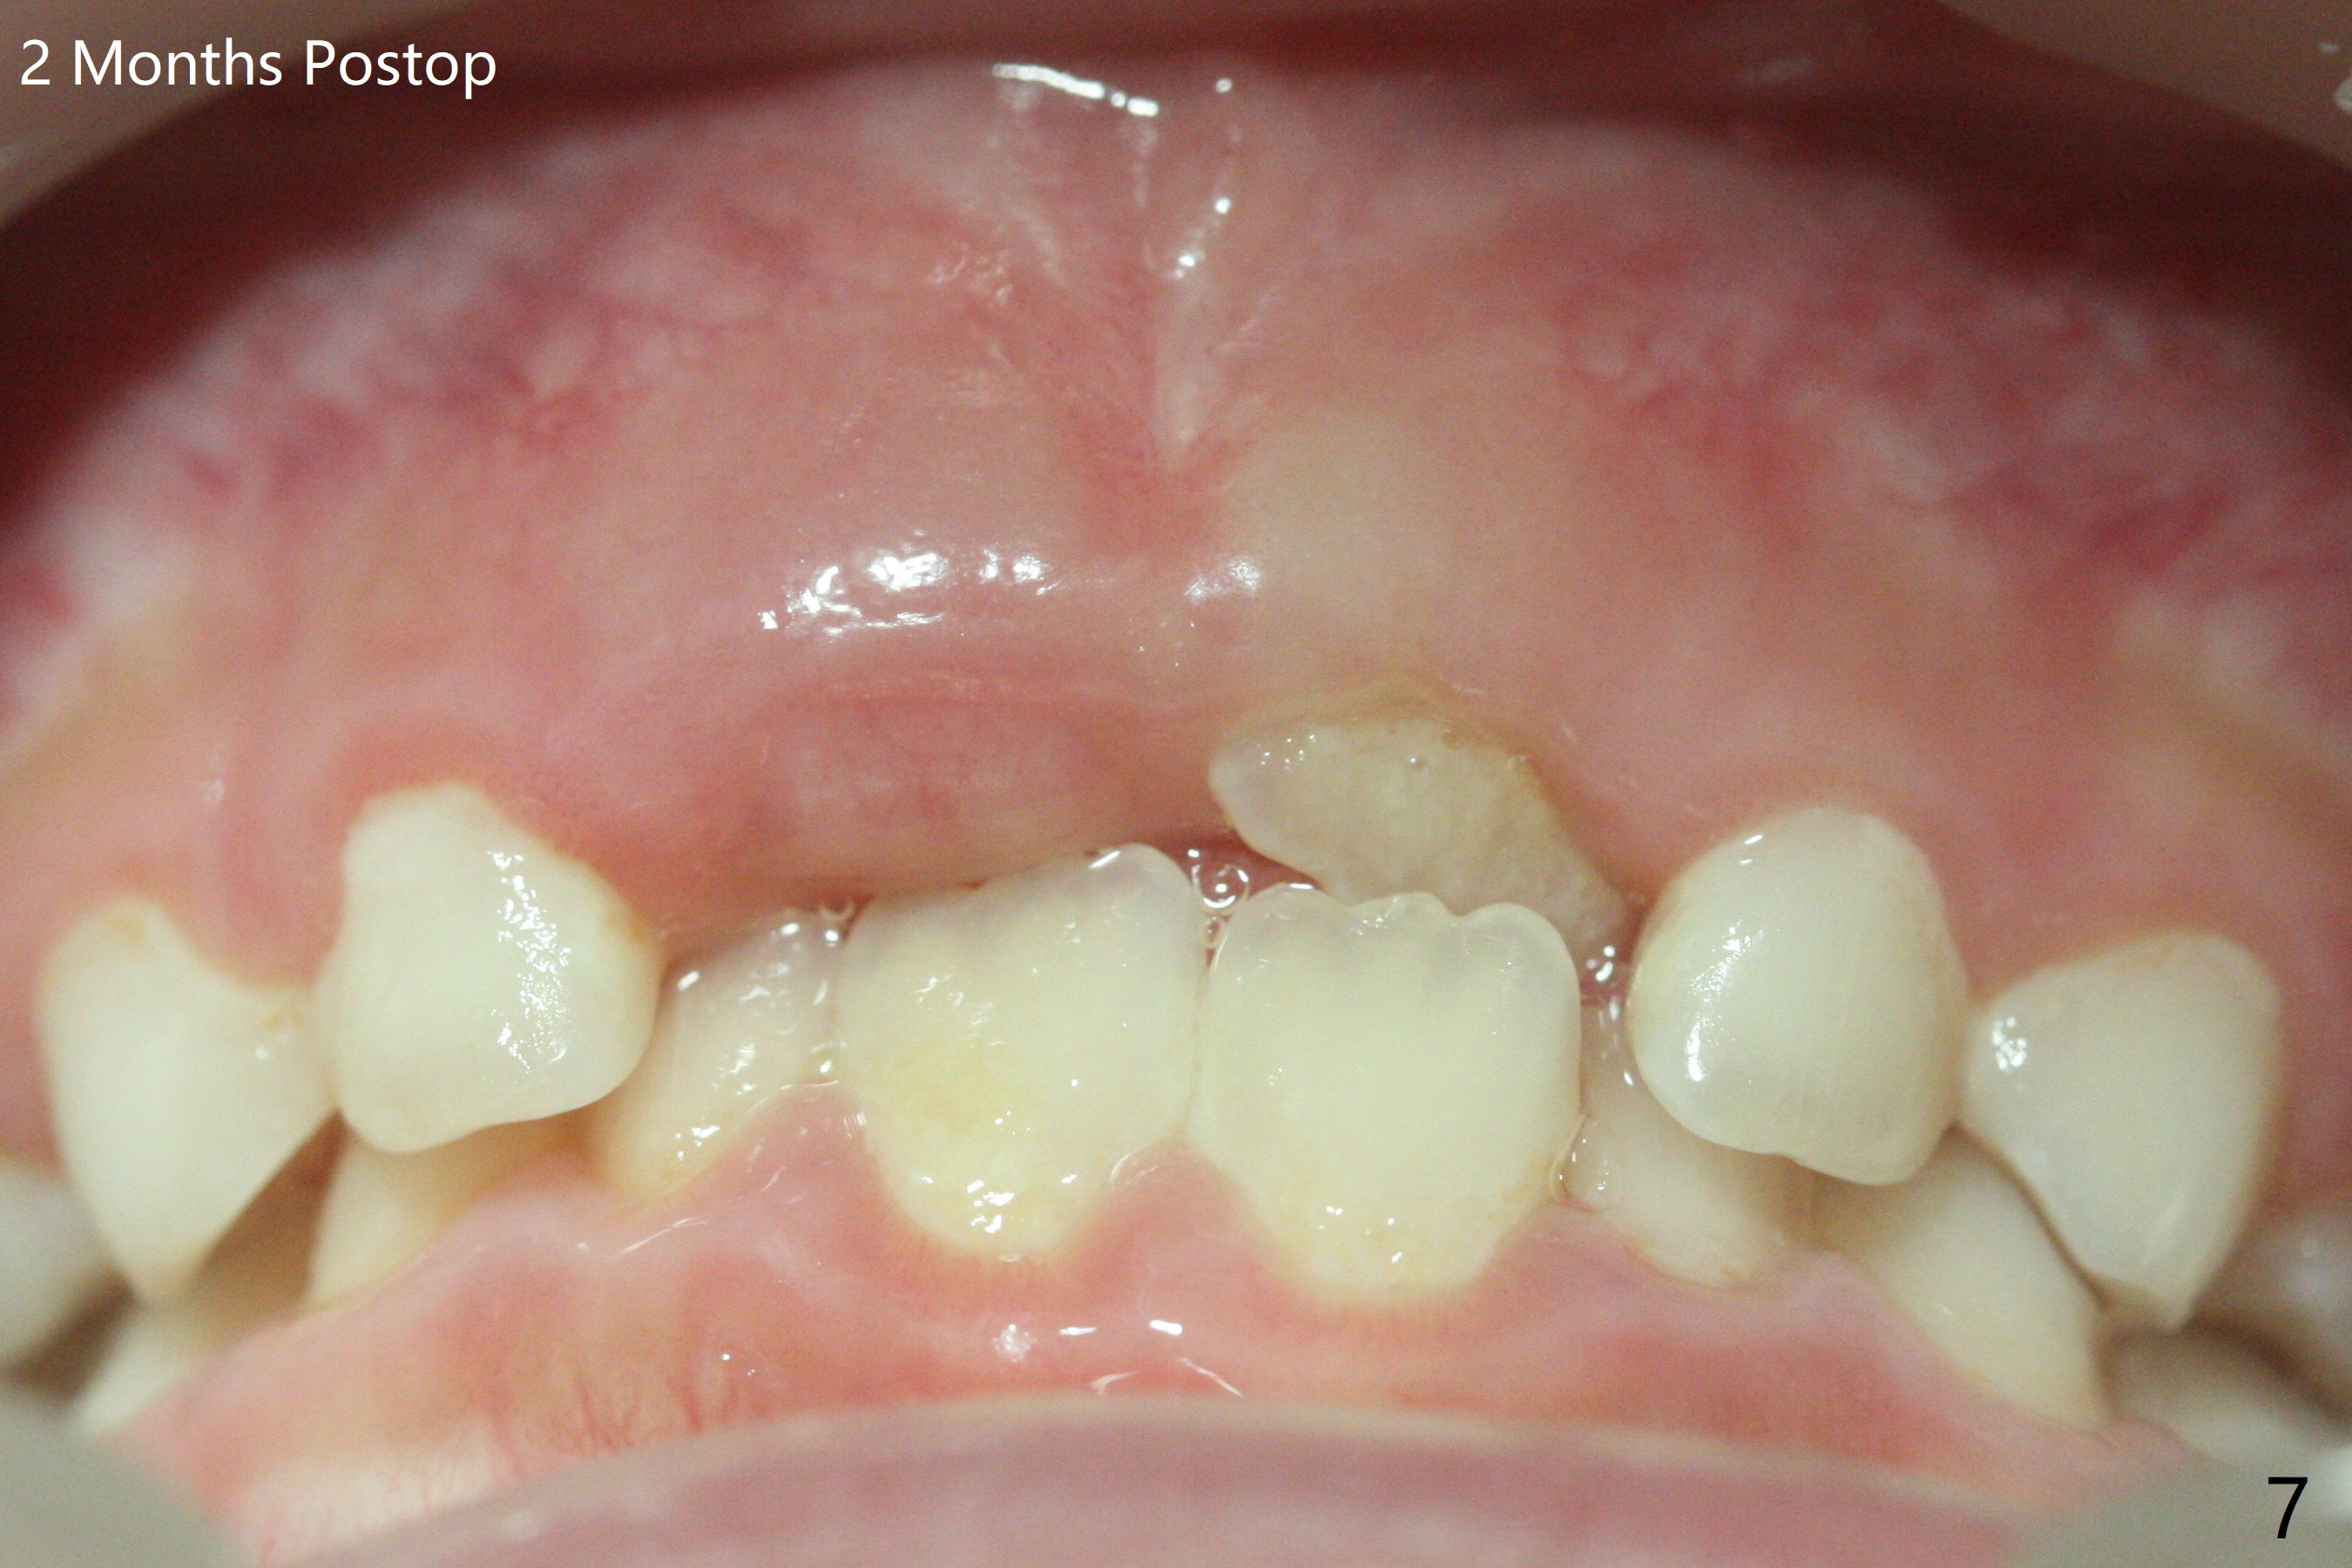

6岁11月女上乳中切牙松动许久,但不脱落,根尖片显示正中多生牙(图一:M),CT显示后者位于腭侧(图二:P)。Take preop photos to show whether the lower lateral incisors have erupted or not. If yes, remove the upperdeciduous central incisors. 一个月后病人回来时,右上乳中切牙已脱落,左上松动 ,术中后者好像影响视野而拔除,腭侧切口,暴露左上1后,拔除多生牙(图三)。 术后3个星期左上中切牙萌出,扭转,反合(图四,五)。术后六个月仍旧如此(图六,七),右上中切牙未萌出,小孩害怕促进萌出手术。准备制作活动矫正器。